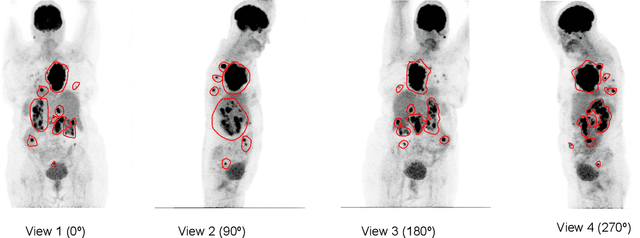

Abstract:An automatic evidential segmentation method based on Dempster-Shafer theory and deep learning is proposed to segment lymphomas from three-dimensional Positron Emission Tomography (PET) and Computed Tomography (CT) images. The architecture is composed of a deep feature-extraction module and an evidential layer. The feature extraction module uses an encoder-decoder framework to extract semantic feature vectors from 3D inputs. The evidential layer then uses prototypes in the feature space to compute a belief function at each voxel quantifying the uncertainty about the presence or absence of a lymphoma at this location. Two evidential layers are compared, based on different ways of using distances to prototypes for computing mass functions. The whole model is trained end-to-end by minimizing the Dice loss function. The proposed combination of deep feature extraction and evidential segmentation is shown to outperform the baseline UNet model as well as three other state-of-the-art models on a dataset of 173 patients.

Abstract:Lymphoma detection and segmentation from whole-body Positron Emission Tomography/Computed Tomography (PET/CT) volumes are crucial for surgical indication and radiotherapy. Designing automatic segmentation methods capable of effectively exploiting the information from PET and CT as well as resolving their uncertainty remain a challenge. In this paper, we propose an lymphoma segmentation model using an UNet with an evidential PET/CT fusion layer. Single-modality volumes are trained separately to get initial segmentation maps and an evidential fusion layer is proposed to fuse the two pieces of evidence using Dempster-Shafer theory (DST). Moreover, a multi-task loss function is proposed: in addition to the use of the Dice loss for PET and CT segmentation, a loss function based on the concordance between the two segmentation is added to constrain the final segmentation. We evaluate our proposal on a database of polycentric PET/CT volumes of patients treated for lymphoma, delineated by the experts. Our method get accurate segmentation results with Dice score of 0.726, without any user interaction. Quantitative results show that our method is superior to the state-of-the-art methods.

Abstract:PET and CT are two modalities widely used in medical image analysis. Accurately detecting and segmenting lymphomas from these two imaging modalities are critical tasks for cancer staging and radiotherapy planning. However, this task is still challenging due to the complexity of PET/CT images, and the computation cost to process 3D data. In this paper, a segmentation method based on belief functions is proposed to segment lymphomas in 3D PET/CT images. The architecture is composed of a feature extraction module and an evidential segmentation (ES) module. The ES module outputs not only segmentation results (binary maps indicating the presence or absence of lymphoma in each voxel) but also uncertainty maps quantifying the classification uncertainty. The whole model is optimized by minimizing Dice and uncertainty loss functions to increase segmentation accuracy. The method was evaluated on a database of 173 patients with diffuse large b-cell lymphoma. Quantitative and qualitative results show that our method outperforms the state-of-the-art methods.